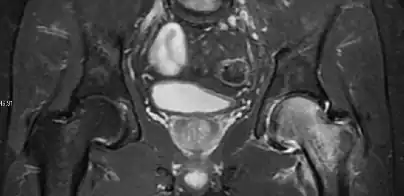

Most of the angles and measurements described in the plain radiograph section can be accurately reproduced on MRI. In addition, the superiority of MRI resolution with intra-articular contrast allows detection of labral and chondral abnormalities that may influence the choice of medical, percutaneous, or surgical management (Figure 9).[1]

Figure 9:

MR arthrography has proven superior in accuracy when compared to native MR imaging. It is considered the best technique to assess the labrum. Knowledge of the normal variable morphology of the labrum helps to differentiate tears from normal variants. A triangular shape is most commonly seen in 66% of asymptomatic volunteers, but round, flattened, and absent labra can also be found in asymptomatic populations. MR arthrography has demonstrated sensitivity over 90% and specificity close to 100% in detecting labral tears. Loose bodies are demonstrated as filling defects surrounded by the hyperintense gadolinium.[1]

Association between labral tears and chondral damage has been demonstrated. This underscores the interaction between cartilage and labrum damage in the progression of osteoarthritis. Chondral damage to the posteroinferior part of the acetabulum as a contrecoup lesion occurs in approximately one-third of pincer cases secondary to persistent abutment on the anterior part of the joint leading to a slight posteroinferior subluxation. This is considered a bad prognosis sign.[1]

MR arthrography can also demonstrate ligamentum teres rupture or capsular laxity, which are debated causes of microinstability of the hip. Elongation of the capsule or injury to the iliofemoral ligament or labrum may be secondary to microtrauma in athletes. MR can demonstrate abnormalities in these cases, such as increased joint volume or a ligamentum teres tear (Figure 9).[1]